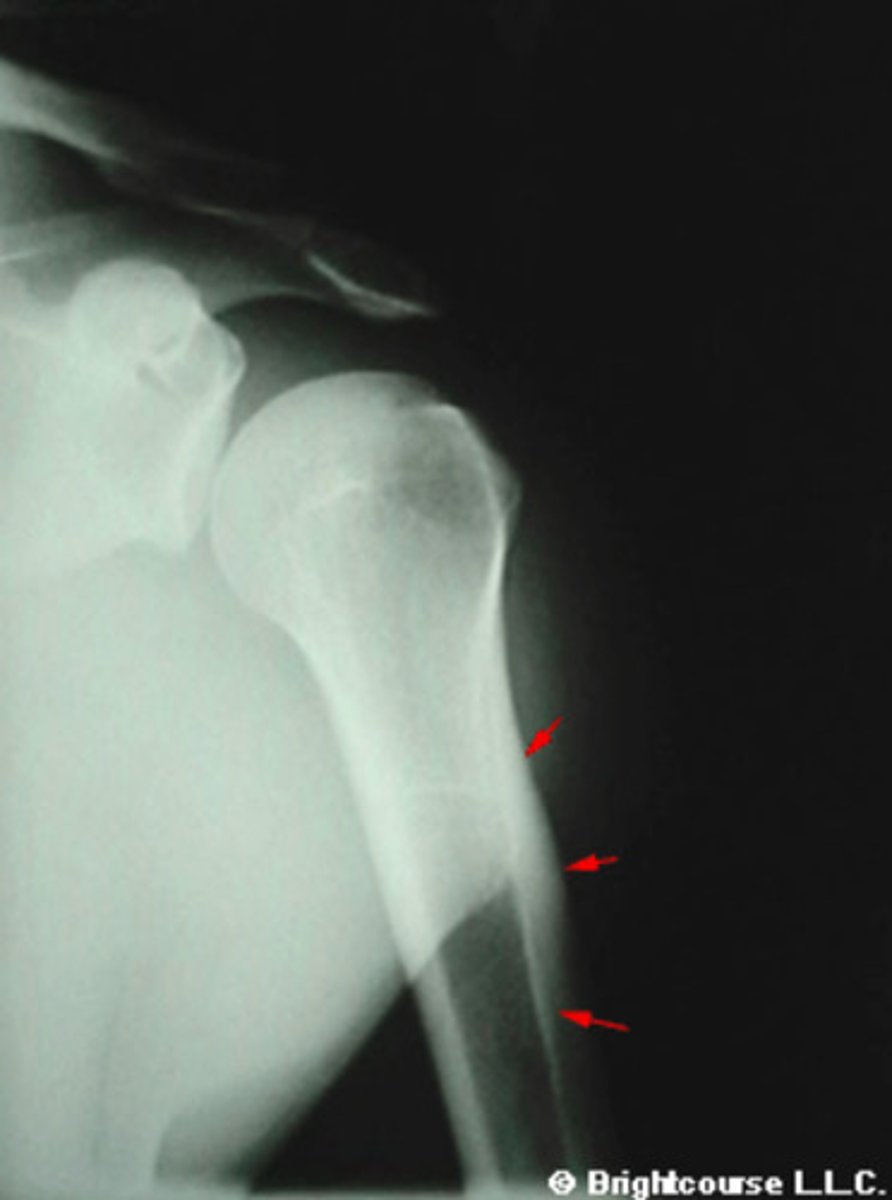

Proximal shaft of humerus

What is being pointed out by the arrows in the image?